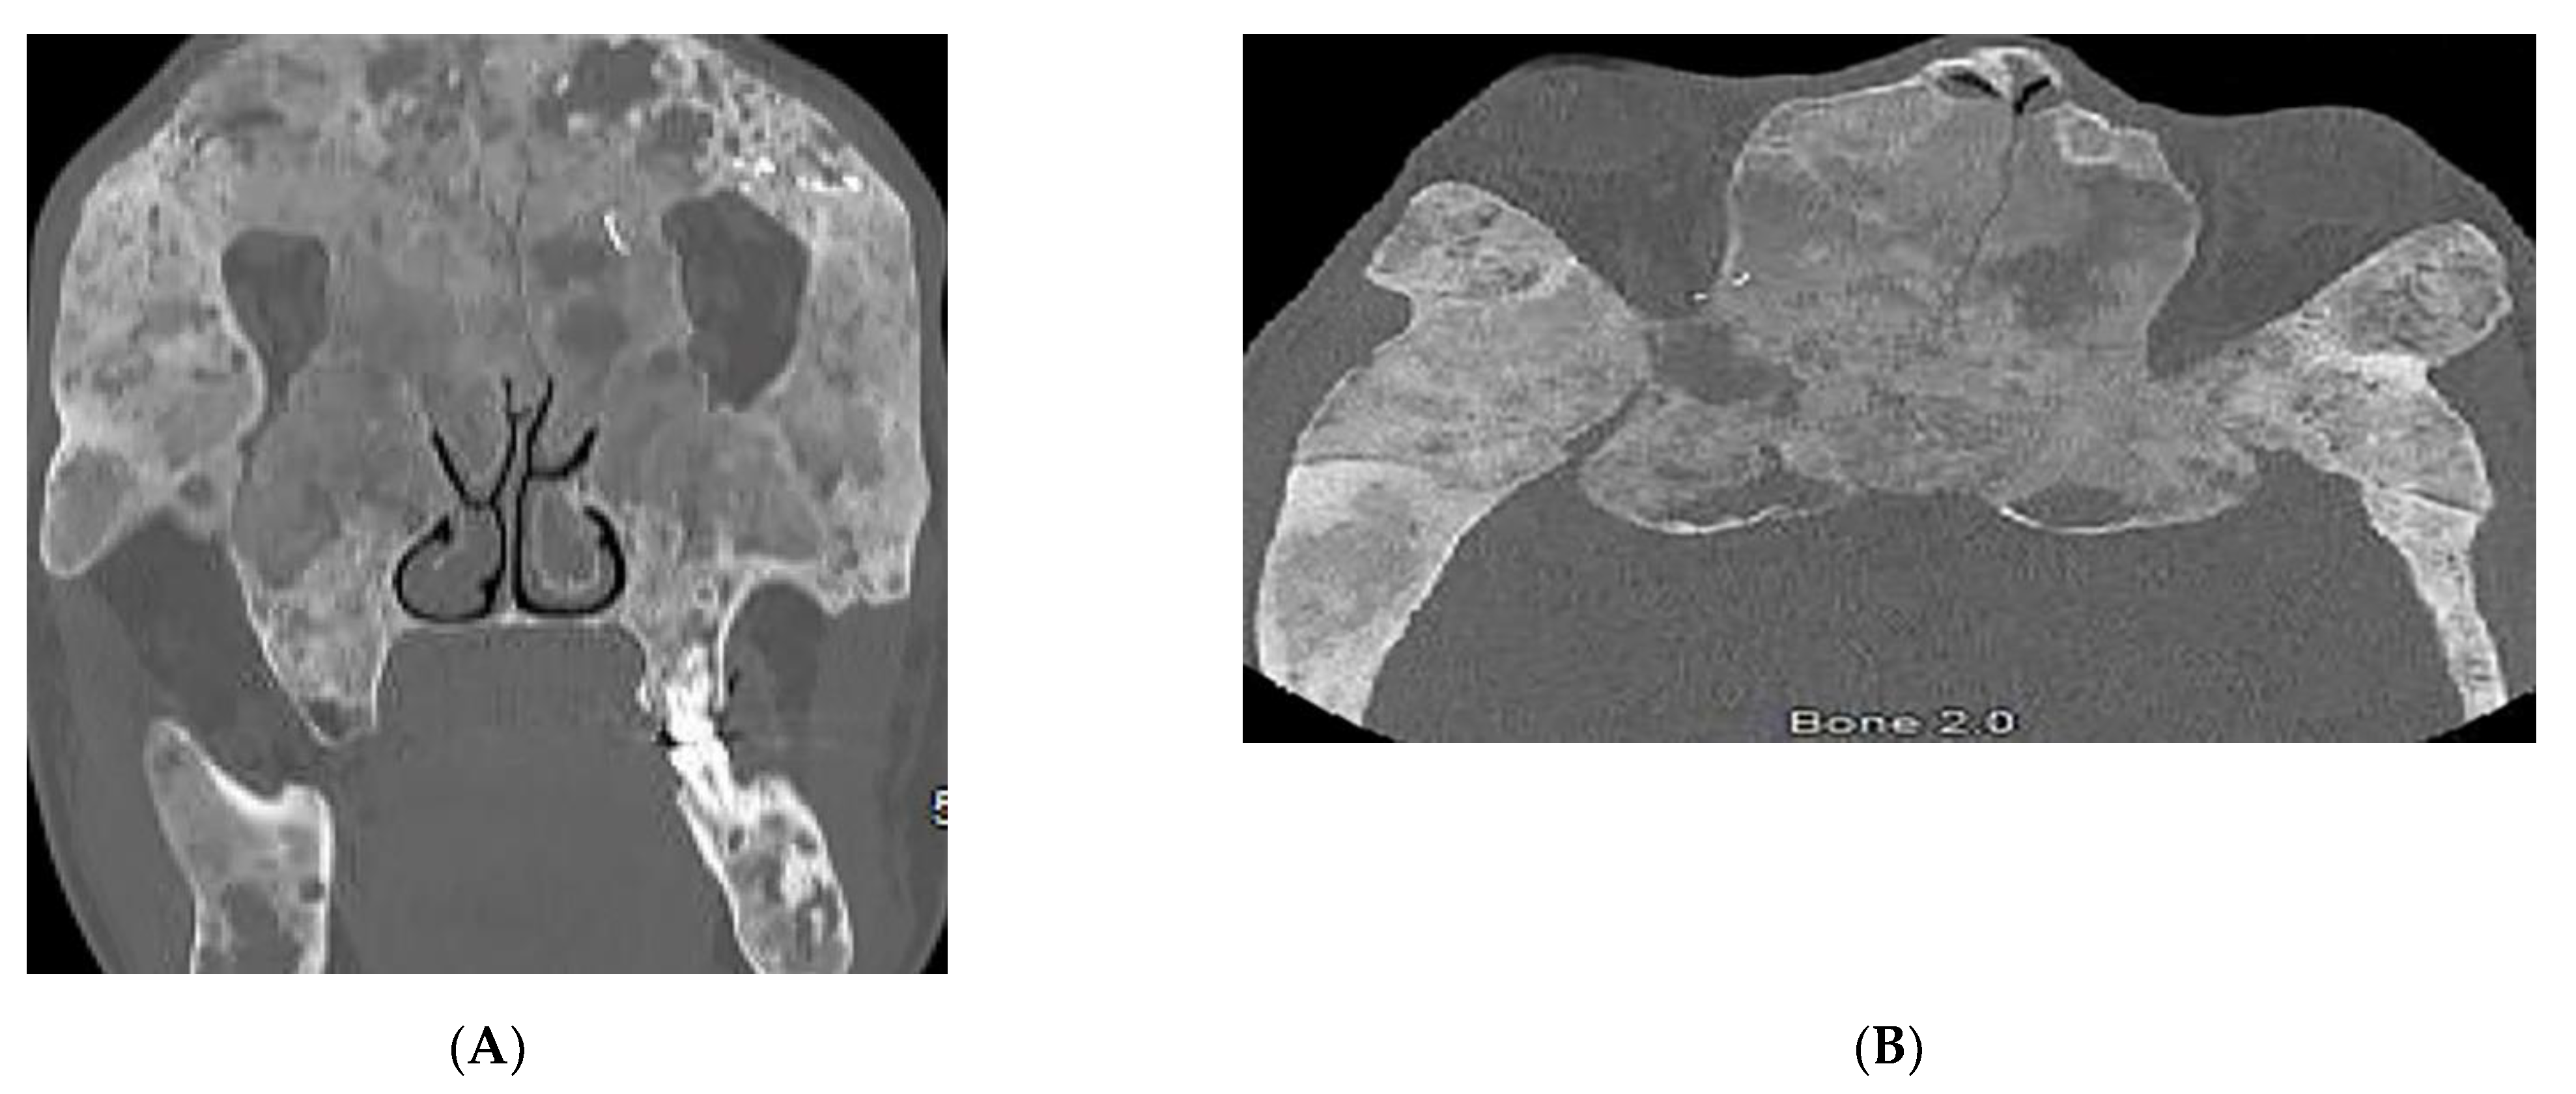

| Basal cell nevus syndrome | Basal cell carcinomas Palmoplantar pits Skeletal abnormalities Brain abnormalities | Keratocystic odontogenic tumors Ribs and metacarpals abnormalities Medulloblastoma, falx cerebri calcification |